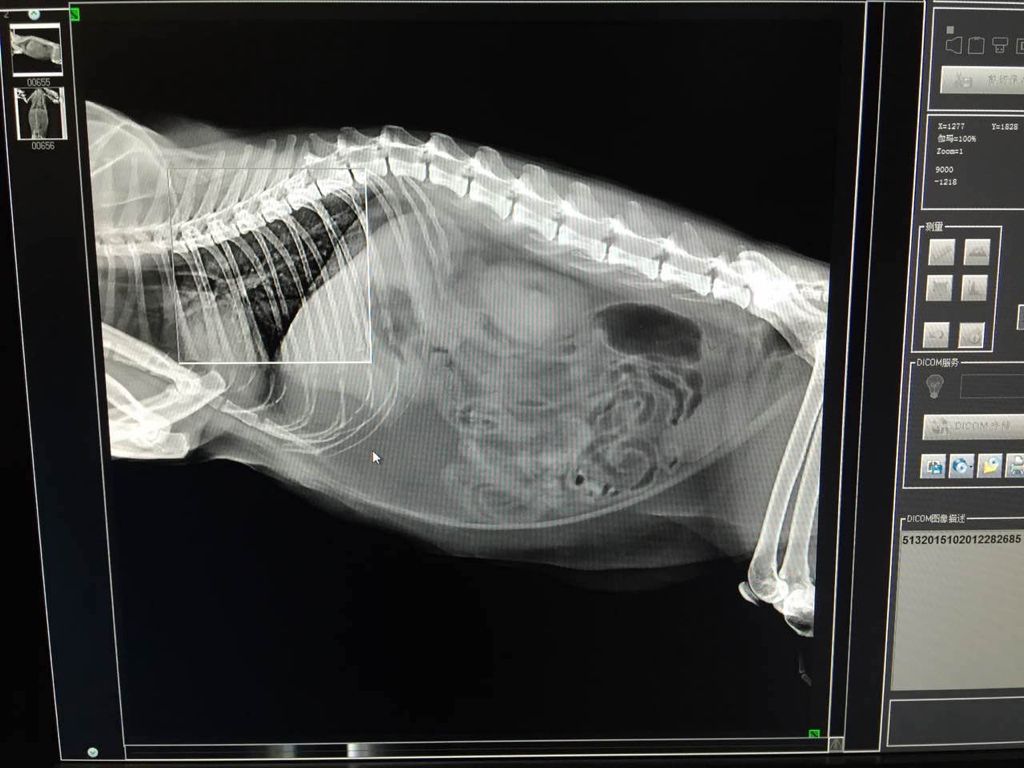

2.对身体内部的损伤,需要进行X射线检查。受伤部位如果是特定的,则以该部位为中心拍X线片,一张胶片可以拍从前胸到骨盆的整个范围,遇到交通事故且临床症状严重的猫必需拍片。通过X线片可以明确是否有骨折、皮下气肿、气胸、血胸及横膈膜穿孔等,进而进行手术治疗。